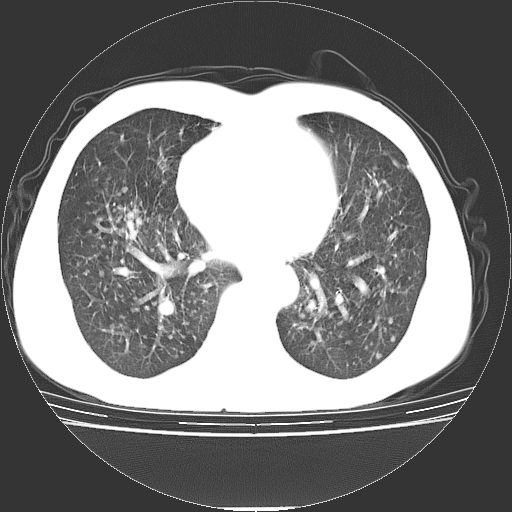

以下是引用yangyudong333在2008-4-29 5:38:00的发言:[br]比较典型的矽肺结节.支持[br]诊断依据:[br] 1.x线表现:[br] ①典型矽肺为多发直径 1~3mm 小结节,即矽结节,由胶原纤维和硅尘构成,可融合成团块,好发于上肺。[br] ②团块周围常有肺大泡。[br] ③胸内淋巴结增大、钙化。如肺门淋巴结呈蛋壳样钙化有助于与其他尘肺区别。[br] ④胸膜常广泛粘连、增厚。[br] 2.ct表现[br] ①两肺散在大小较为一致的小结节影,其密度较高,边界清楚。[br] ②小结节可融合为较大团块影,直径约 1cm ,甚至可达 10cm以上,易发生在上叶。[br] ③小结节周围常并有小叶中心气肿或弥漫性肺气肿。

以下是引用liuyue在2008-4-28 22:30:00的发言:[br]比较典型的矽肺结节.[br]请结合临床及化验除外矽肺合并肺结核之可能.